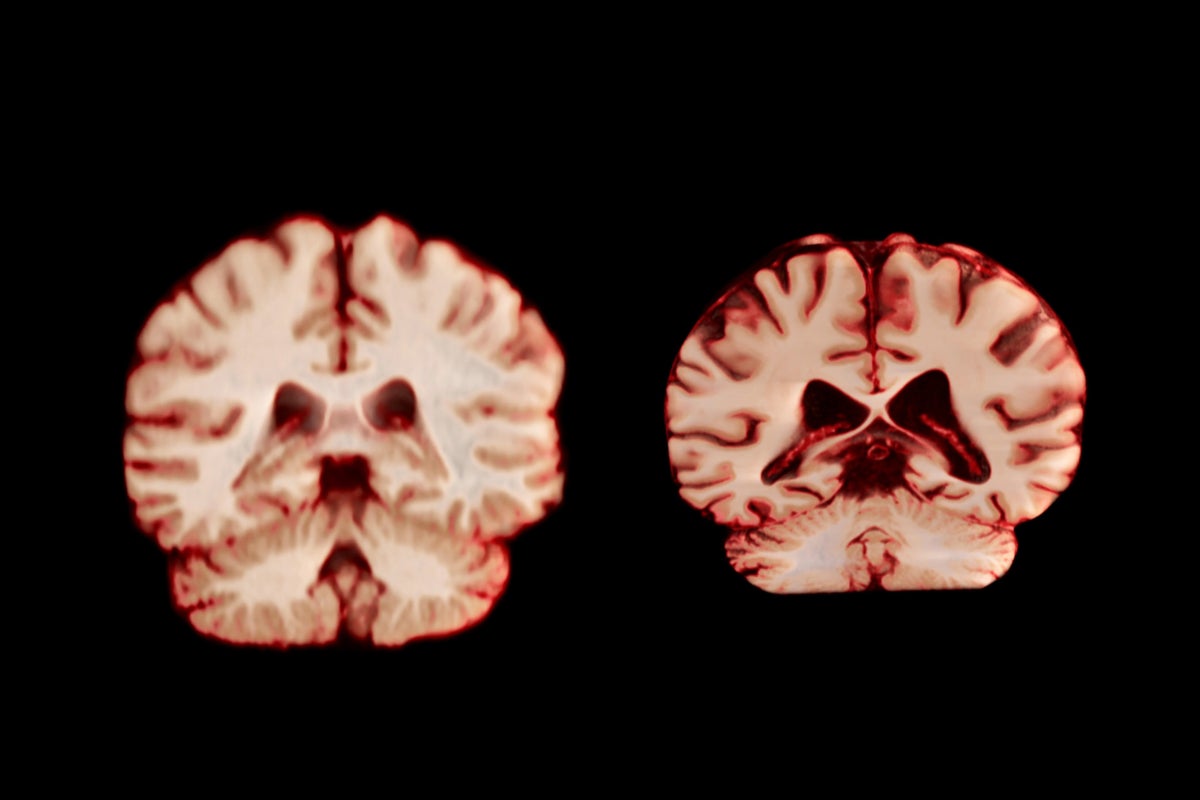

Researchers studying brain-imaging data from people aged between 8 and 100 found that sex differences in the brain's connections are minimal in early life, but then increase drastically at puberty; some of these differences continue to grow throughout adult life. The study was published as a preprint on bioRxiv, and has not yet been peer reviewed. The work could help us to understand why men and women have different likelihoods of developing some mental-health disorders - and perhaps give insight into treating them, say the researchers.